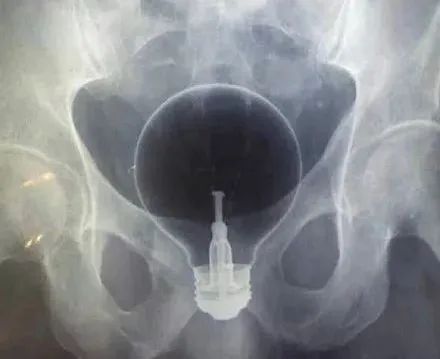

案例二:众所周知,灯泡放在人体内的两个地方,是绝对无法自己取出的。一个是嘴巴,另一个是菊花。这位男子就把灯泡塞进了肛门。